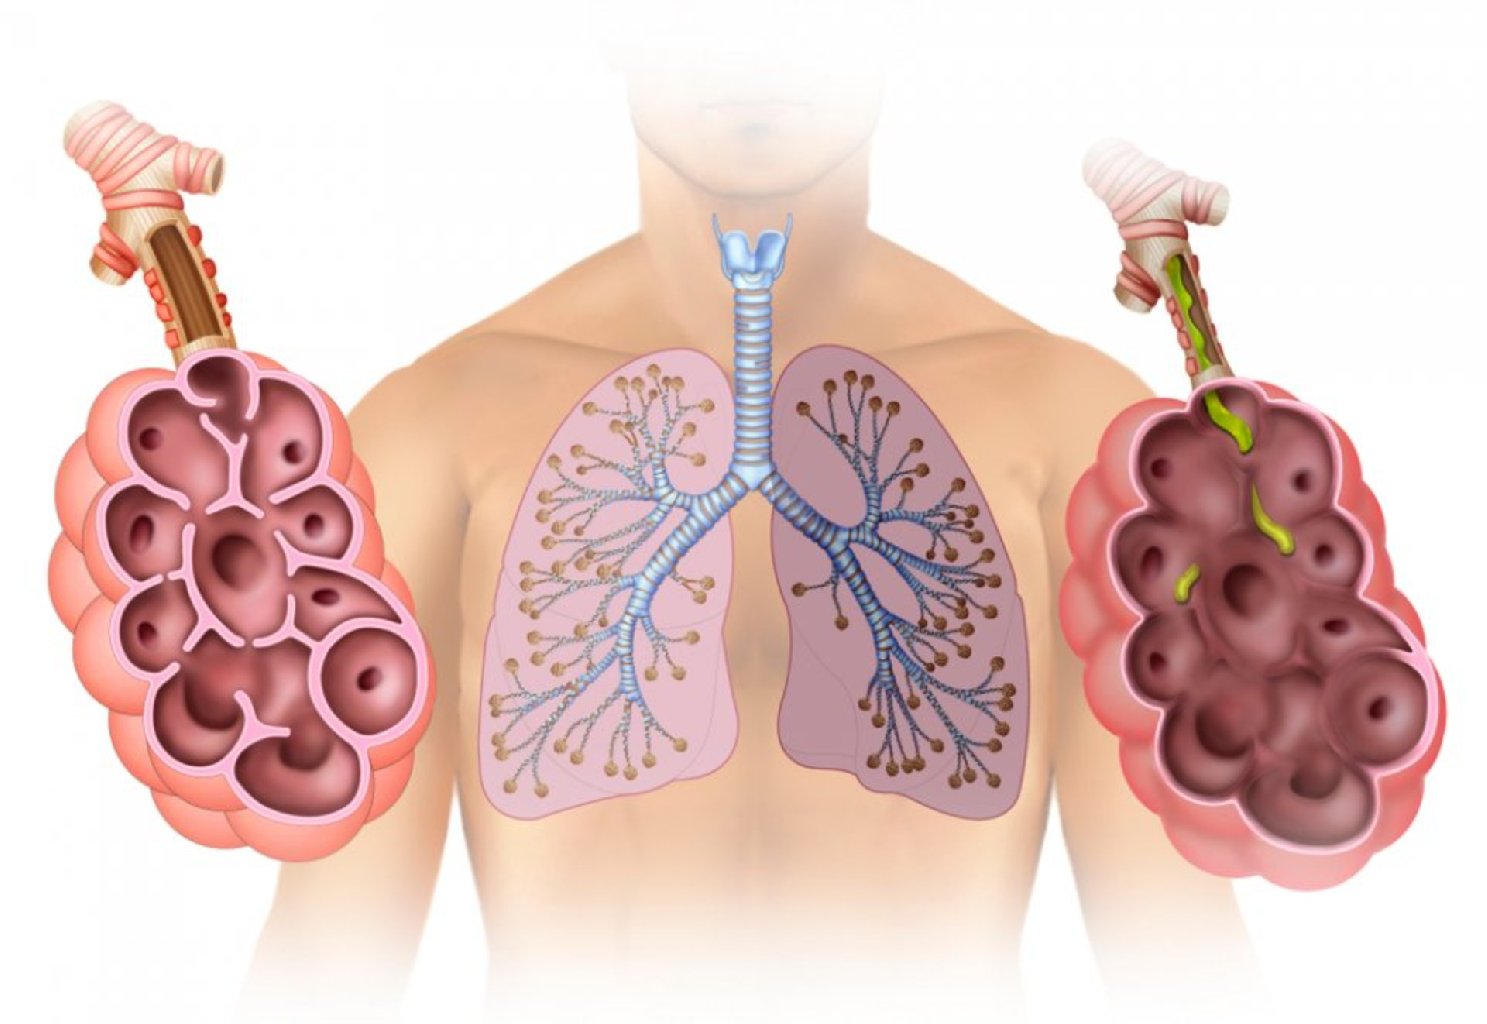

Alveolların zədələnməsi: Ağciyərlərdəki alveollar normal olaraq hava ilə doldurulur və boşalır, oksi ...

Ağciyər Absesi: Bu, ağciyər toxumasında yaranan irinli bir cavab olup, adətən bakterial infeksiya nə ...